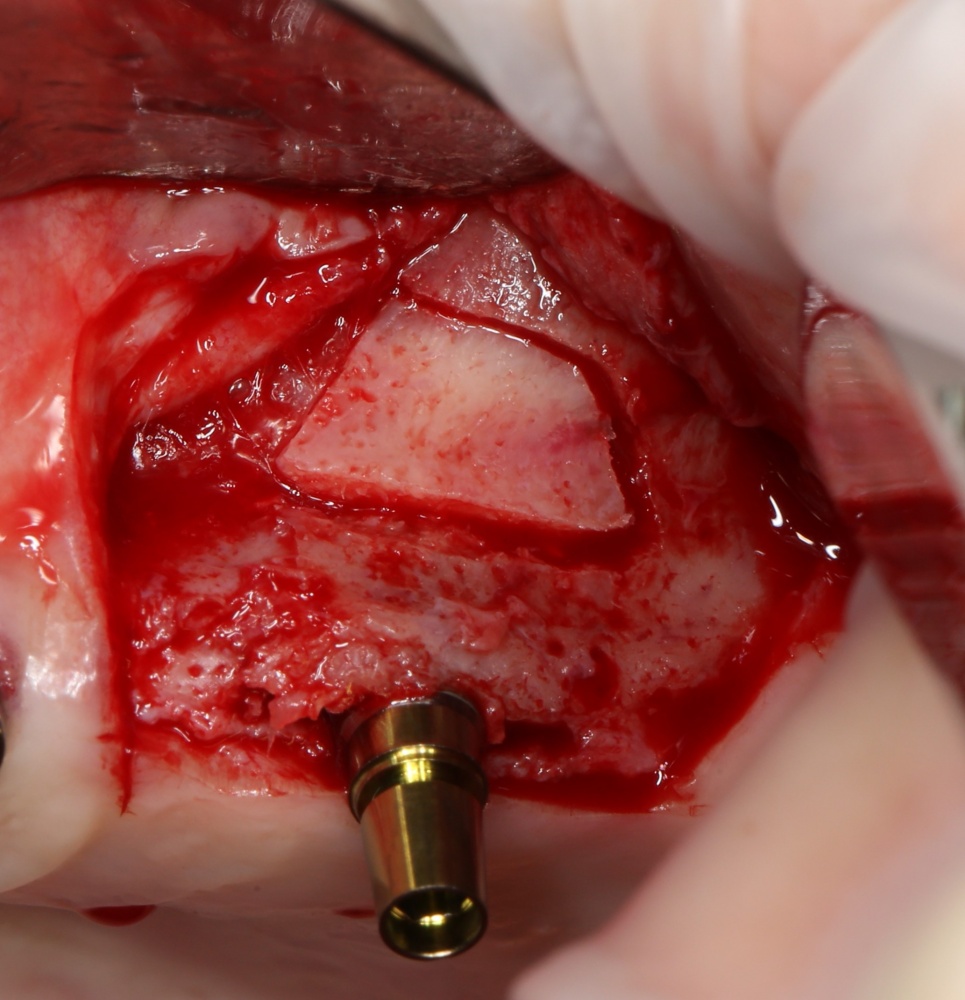

Для получения костного блока, мы открываем донорскую зону, наружную косую линию нижней челюсти.

Получение костного аутотрансплантата.

Здесь потребуется пародонтологический зонд с миллиметровой разметкой или какой-то другой измерительный прибор (операционная линейка). Ранее по КЛКТ я измерил костный дефект, теперь нужно нанести границы будущего костного блока на донорскую зону.

Ремарка: некоторые доктора предлагают делать хирургические шаблоны или выкройки специально для точного забора костного блока. На мой взгляд, это чрезмерное усложнение - во-первых, использование подобных шаблонов или выкроек требует увеличения площади раны, во-вторых, это увеличивает время и стоимость лечения, в-третьих, на этом этапе не требуется высокая точность, поскольку блок всё равно потребует адаптации.

Иными словами, важна не точность, а быстрый, аккуратный и, что главное, малотравматичный забор аутотрансплантата.

Для получения костного блока мы использовали ультразвуковую пьезохирургическую систему. Это самый удобный и безопасный инструмент для проведения подобных манипуляций. С помощью него мы сформировали и выделили костный блок. Он должен отделяться легким движением остеотома или элеватора. Как это сделать правильно — читай здесь>>

Кстати, если костный блок не отделяется от костного ложа легким движением элеватора, значит он неправильно сформирован или не до конца выделен. Вообще, любое чрезмерное усилие в хирургии — это всегда следствие рукожопия. Если тебе что-то приходится делать с усилием (установка имплантата, удаление зуба и т. д.) — значит ты делаешь это неправильно. Остановись и подумай, что именно.